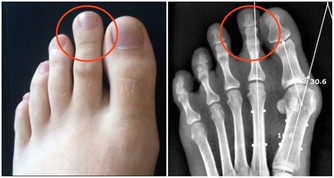

對於小孩子來說,隨著生長速度加快,可能就會造成缺鈣,骨骼疼痛,而對於女性朋友來說,到了絕經期,鈣元素流失更會加快,容易出現骨質疏鬆,而對於老年人來說,如果不補鈣也會導致骨骼變得脆弱,容易發生骨折的風險。